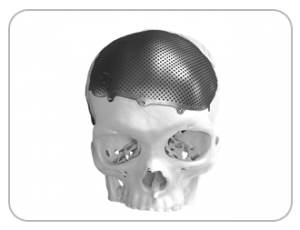

“Medicad Implants becomes the first indian company to design and manufacture porous cranial implants.”

By way of helping Mrs. Kamala regain her confidence and live a worry-free life, Medicad Implants LLP became the first company in India to design and manufacture porous titanium implant India. Her life took a U turn when she suffered a stroke and had to loose a large part of her skull during the surgery. She found it difficult to sleep on one side and even to meet her family members was a nightmare. Titanium implant India were suggest for the best possible outcome from cranioplasty.

DEFECT DUE TO STROKE

DESIGNED IMPLANT

IMPLANT FABRICATED WITH POROUS TITANIUM